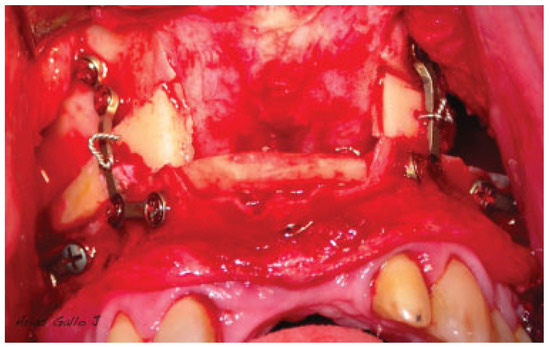

Figure 1.

Fixation of the bone blocks with a wire that goes beyond the graft and anchors the plates.